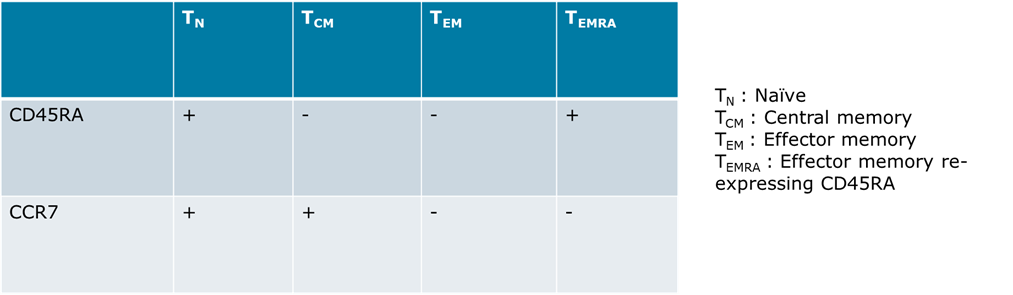

T Cell Subsets Defined by Expression of Two Surface Molecules: CD45RA and CCR7

T cells can be divided into four functionally distinct subsets defined by the expression of CD45RA and CCR7 (Ref. 1).

Circulating memory T cells are generally predominantly of the TEMRA phenotype. But this bias is known to be even stronger with CMV-specific T cells. In the tested individual CMV-specific TEMRA make up 83% of the memory T cells.